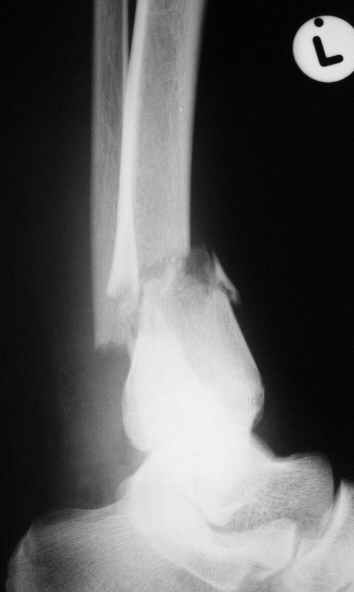

Уважаемые коллеги,Больной 17 лет , 3 недели с момента травмы, был переведен в наше отделение из соседнегогоспиталя.

Попытка закрытой ручной репозиции, предпринятая ранее в этой больнице,оказалась безуспешной, что и явилось причиной перевода к нам.Чтобы вы предложили в данной ситуации?Показана ли фиксация перелома малоберцовой кости в данном случае или в этом нет необходимости?Евгений Чекашкин

На прямой проекции видно угловое смещение отломков малоберцовой кости, обуславливающий и

наклон тарана, да и вальгус отломков б.б. , а на боковой проекции -смещение отломков

кпереди и по длине.

Коррекция углового смещения и смещения по длине отломков м.б. кости автоматом устраняет

наклон тарана , что необходимо для нормальной функции голеностопа. Так оно и произошло во

время операции.